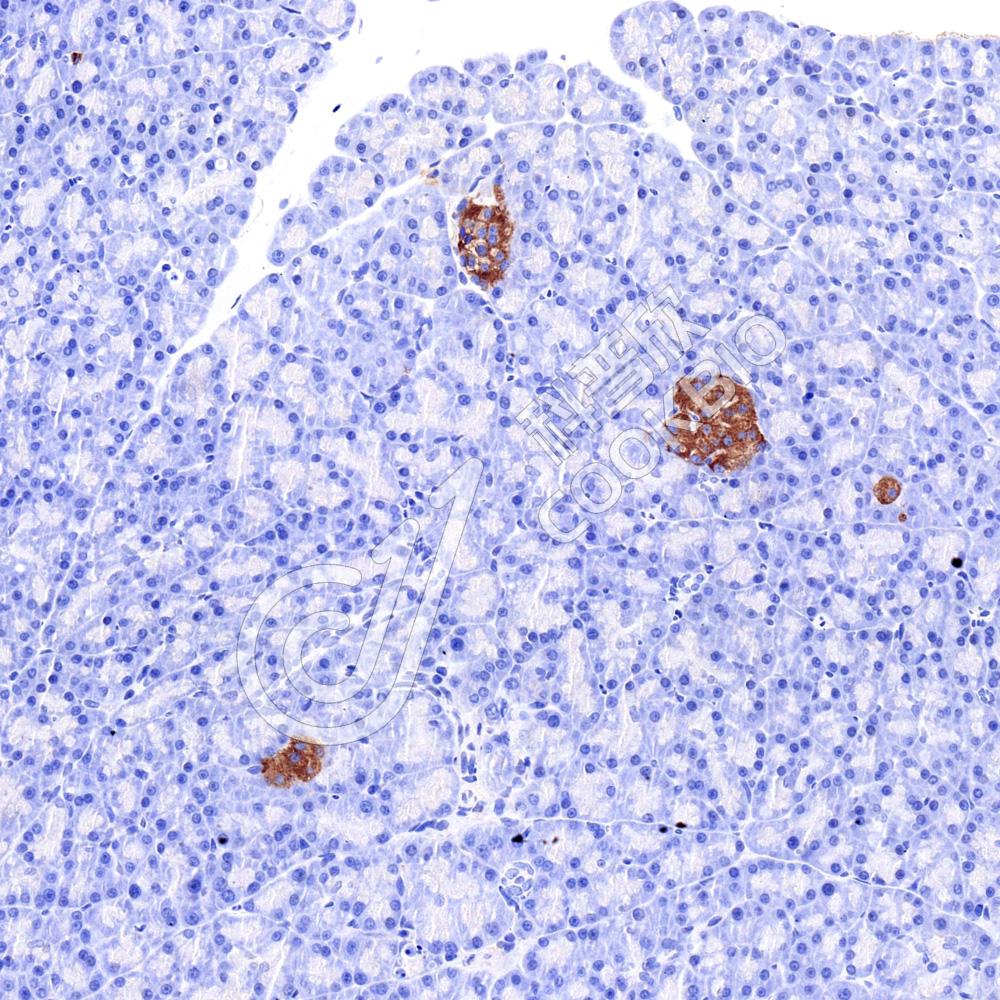

IHC检测REDD-1/DDIT4蛋白(货号 K135811).

样品: 小鼠胰腺, 4%多聚甲醛 (货号KSG1101) 固定12-24小时.

抗原修复: 柠檬酸抗原修复液(干粉, pH 6.0) (KSG1201), 98℃, 20分钟.

—抗: 1: 1800稀释, 4℃ 孵育过夜.

二抗: S-vision免疫组化多聚二抗(山羊抗兔),即用型 (货号KB3906), 室温孵育20分钟.

样品: 大鼠胰腺, 4%多聚甲醛 (货号KSG1101) 固定12-24小时.